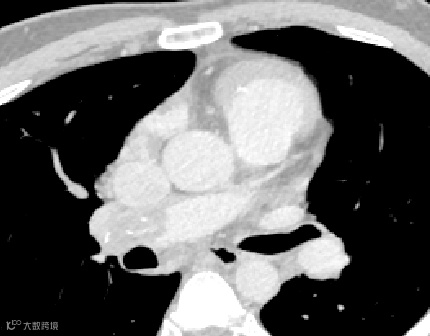

经ct评估,发现患者双肺多发肺动脉栓塞,右肺动脉干远端血栓形成并钙化、主肺动脉稍增宽、右心房血栓形成并钙化可能。针对患者情况,专家们进行多学科会诊,认为该患者情况复杂,建议实施开胸手术取出栓塞物。

考虑患者情况特殊,血栓分布较广,血管外科团队术前采用思源智慧医疗3D打印模型,观察血栓的分布情况,对手术进行规划。降低了手术时间,减少了手术风险,最终手术圆满成功!家属激动地说:“是厦心医院给了他第二次生命”。